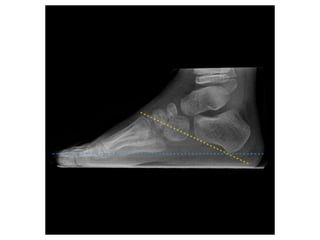

Radiology

• Plain radiograph: Can be assessed prior to

treatment with A-P & Lateral of foot

• Foot held in position of best correction, with weight-

Lateral view

• The lateral talocalcaneal angle

• Meary angle

• Hibb angle

• Calcaneal pitch

Talocalcaneal angle

Angle between

the mid-talar

axis and calcaneal

inclination axis.

-normally measure

between 30° and 45°

-decreased in a varus

foot and increased in a

valgus hindfoot

Meary angle

• B/n long axis of the talus and the long axis of

the 1st MT

• Normally, these lines are colinear

• apex directed dorsally-cavus foot

• apex angled plantarward- valgus or flatfeet

Hibb angle

• angle between the plantar surface of the

calcaneus and the first metatarsal

• Normally Hibb angle is

greater than

150 degrees

Calcaneal pitch

• Angle between the horizontal and the plantar

surface of the calcaneus

• Important in evaluating a cavus foot or

clubfoot

• low: 10-20° - indicative of pes planus

• medium: 20-30°

• high: ≥30° - indicative of pes cavus